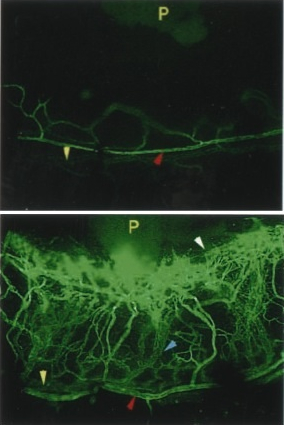

SN-induced angiogenesis

in the limbus vein

(upper panel = control).

Several biological effects have been established for SN. SN releases dopamine from the rat striatum in vivo and in vitro(Saria et al., 1993; Agneter et al., 1995) and has a potent chemotactic effect towards monocytes, eosinophils and endothelial cells (Reinisch et al., 1993; Schratzberger et al., 1997; Kähler et al. 1999). Very recently a potent angiogenic and vasculogenic activity of SN was identified by Kirchmair and Schratzberger (Kirchmair et al., 2004a,b). These effects suggested that SN is involved in conditions contributing to neurogenic inflammation.